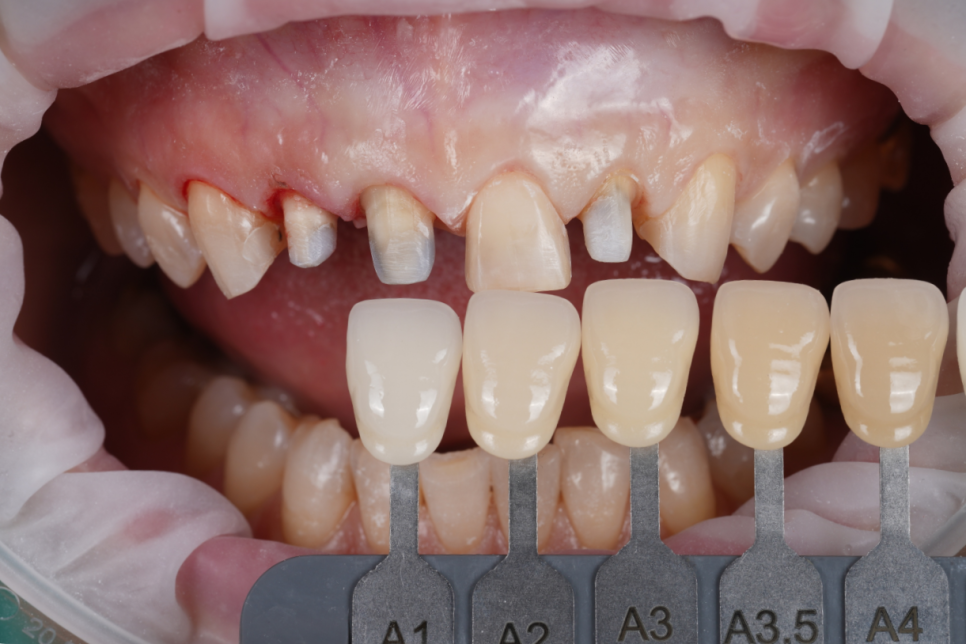

251202

기존 보철을 제거하고 라미네이트 제작을 위해 소량 다듬고 치아 색상을 확인했습니다.

색상도 튀지 않게 하나만 밝아 보이거나 탁해 보이지 않도록 투명도와 명도를 맞추는 데 집중했어요.